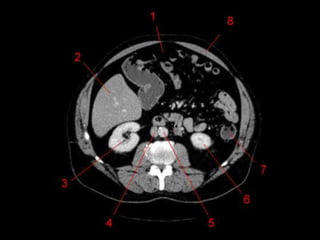

Vias Biliares • Funçãode carrear a bile do fígado para o duodeno. • Intra-hepáticas: 3mm • Bile é produzido continuamente pelo fígado e armazenada na vesícula. • Ductos hepáticos D e E > Ducto hepático comum. (3 – 6 mm) • Ducto Hepático Comum + Ducto Cístico > Ducto Colédoco. ( 8mm)

Ducto Colédoco • 5– 15 cm • Finaliza seu percurso no duodeno (lado medial da porção descendente), passando posteriormente à cabeça do pâncreas. • Se liga ao ducto pancreático no meio do caminho formando a ampola hepatopancreatica (Vater), terminando na papila duodenal maior. (Esfincter de Oddi)

Vesicula Biliar • Localizadona superficie visceral, entre o fígado direito e esquerdo. • 50 ml de bile. • Dividido em Fundo, Corpo, Colo e Infundíbulo. • Peritônio recobre o fundo, e aproxima o corpo e o colo ao fígado • CT: 4-5mm – Parede: 1 – 3,5 mm.